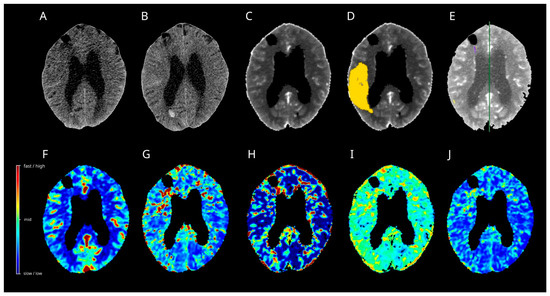

3.10. Case 1

3.11. Case 2